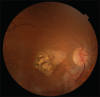

Macular coloboma is a congenital defect of the retina and choroid in the macular region. It may appear due to an intrauterine inflammation or a developmental abnormality. Familial hypomagnesemia with hypercalciuria and nephrocalcinosis (FHHNC) is a result of malformation of the renal tubule. Its combination with ocular manifestations may be genetic, specifically in case of claudin-19 (CLDN-19) gene mutations. The combination of FHHNC and ocular manifestations is not always present in these patients. Optical coherence tomography (OCT) helps us diagnose this condition by allowing us to evaluate and confirm the absence of retina layers without histological examination. Although genetic testing is necessary to diagnose mutational alterations of the CLDN-19 gene, in our case, it was not necessary to diagnose the FHHNC patient with macular coloboma, since the diagnosis of ocular damage had been already accurately established by the OCT.